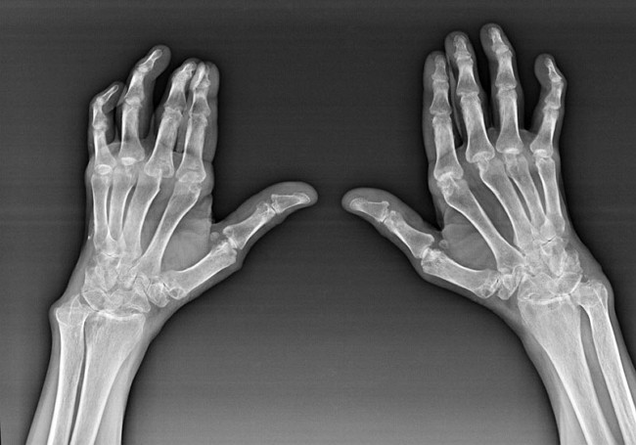

Trotz der Tatsache, dass rheumatoide Arthritis in größerem Maße eine systemische Krankheit ist, leiden die Gelenke, während die Verletzung anderer Gewebe und Organe im Hintergrund liegt. Mit dieser Krankheit können fast alle Arten von Bürsten beeinflusst werden (Zeichnungen aus Handgelenk, Karpalgefahren, Metacarpal-Falan-Gelenke, Inter-Falan). Die Läsion ist im Allgemeinen symmetrisch (diese. Die gleichen Gelenke sind interessiert) an beiden Händen, begleitet von Schwellungen, Schmerzen in beschädigten Gelenken. Am Morgen, während des Hebens aus dem Bett, gibt es in den betroffenen Gelenken ein wenig Starrheit, die etwa 1 Stunde dauern und dann spurlos verschwinden können.

Sehr oft mit rheumatischer Arthritis in der Nähe der betroffenen Gelenke der Bürste (Häufiger die Articop-Falan-Gelenke, Schnittstellen) Rheumatoide Knötchen erscheinen. Sie sind eine abgerundete Formation, die sich unter der Haut befindet. Auf dem Pinsel entstehen diese Formationen häufiger auf der Rückseite. Bei Palpation sind sie dicht, inaktiv und schmerzlos. Die Anzahl von ihnen kann variieren.